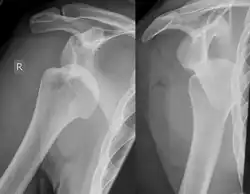

Diagnosis can be suspected by history and physical examination which is usually followed by imaging. Because of the mechanism of injury, apprehension of anterior dislocation is common with provocative maneuvers. Hill–Sachs lesions have been classified as "engaging" or "non-engaging", with engaging lesions defined by the ability of the glenoid to sublux into the humeral head defect during abduction and external rotation. Engaging dislocations have a higher risk of recurrent anterior dislocation, and their presence can help guide surgical management.[2] Imaging diagnosis conventionally begins with plain film radiography. Generally, anteroposterior (AP) radiographs of the shoulder with the arm in internal rotation offer the best yield while axillary views and AP radiographs with external rotation tend to obscure the defect. However, pain and tenderness in the injured joint make appropriate positioning difficult and in a recent study of plain film x-ray for Hill–Sachs lesions, the sensitivity was only about 20%. i.e. the finding was not visible on plain film x-ray about 80% of the time.[3]

By contrast, studies have shown the value of ultrasonography in diagnosing Hill–Sachs lesions. In a population with recurrent dislocation using findings at surgery as the gold standard, a sensitivity of 96% was demonstrated.[4] In a second study of patients with continuing shoulder instability after trauma, and using double contrast CT as a gold standard, a sensitivity of over 95% was demonstrated for ultrasound.[5] It should be borne in mind that in both those studies, patients were having continuing problems after initial injury, and therefore the presence of a Hill–Sachs lesion was more likely. Nevertheless, ultrasonography, which is noninvasive and free from radiation, offers important advantages.

MRI has also been shown to be highly reliable for the diagnosis of Hill-Sachs (and Bankart) lesions. One study used challenging methodology. First of all, it applied to those patients with a single, or first time, dislocation. Such lesions were likely to be smaller and therefore more difficult to detect. Second, two radiologists, who were blinded to the surgical outcome, reviewed the MRI findings, while two orthopedic surgeons, who were blinded to the MRI findings, reviewed videotapes of the arthroscopic procedures. Coefficiency of agreement was then calculated for the MRI and arthroscopic findings and there was total agreement ( kappa = 1.0) for Hill-Sachs and Bankart lesions.[6]